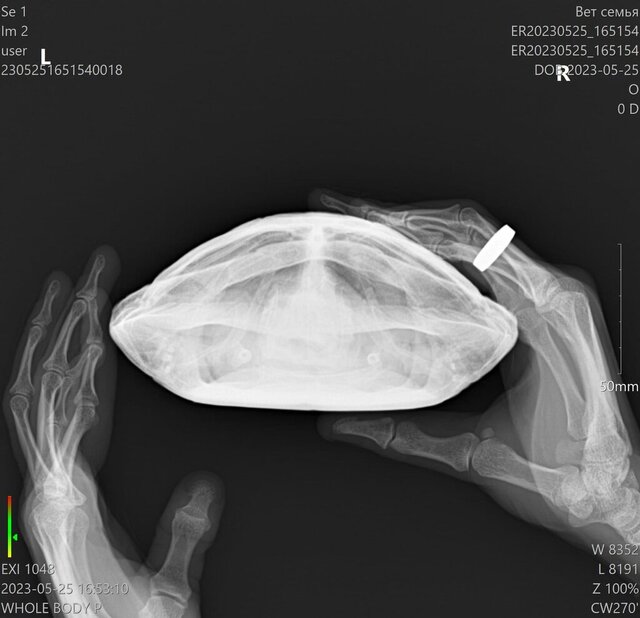

Добрый вечер. Сделали рентген. Нашла герпетолога у нас в городе, сказали на рентгене есть очаги небольшие. Поставили диагноз Гиповитаминоз А, пневмония. Лечение назначали (скинула фото). Этого достаточно? На их весах вес оказался меньше (около 700 грамм).

958506B8-2396-4F3A-865C-AE9AA77D2C6A.jpeg

9B71F9A2-2700-4060-A552-26B9AFA17E85.jpeg

image.jpg